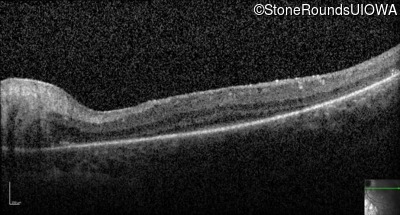

Optical Coherence Tomography - Right -

No Light Perception

Exemplar

Expanded OCT Stack

×